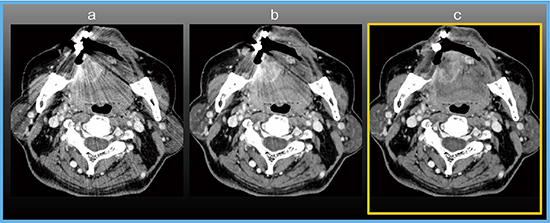

症例4は右舌縁がんの症例であり,FIRSTを用いることでインプラント(義歯)からのストリークアーチファクトが低減し,腫瘍が鮮明に描出されている(図8 b)。さらに,FIRSTにSEMARを適用することでダークバンドアーチファクトも低減され,相乗効果によって,ほぼ金属アーチファクトの影響のない画像が得られた(図8 c)。

図8 症例4:右舌縁がん(T3)

a:FBP b:FIRST c:FIRST+SEMAR